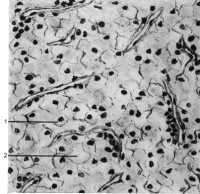

Mikroskopisch wird das Bild von klarzelligen, zum Teil drüßenschlauchähnlichen (tubulären) oder soliden Strukturen dominiert (Abbildung 2). Die hellen Zellen sind pflanzenähnlich und mit glykogen gefüllt. Im Weiteren finden sich Nekrosen und Blutungen.